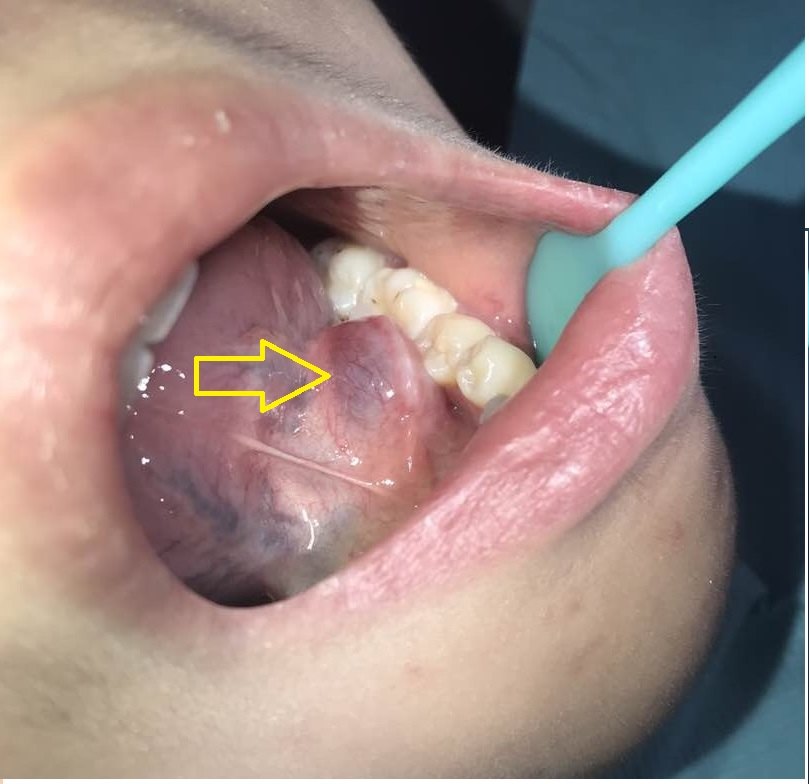

舌下腺囊肿

舌下腺囊肿早期图片 舌下腺囊肿发病部位不同,临床表现也不一样。单纯型舌下腺囊肿位于舌下区,破裂后有蛋清

指导意见:这种舌下腺囊肿,与腺体导管堵塞有直接关系,这种情况属于良性改变,但是需要通过手术才能改善